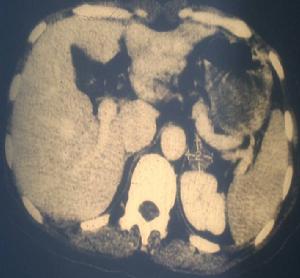

引起醛固酮增多症的腎上腺皮質腺瘤大多比較小,B超、CT、同位素標記膽固醇作腎上腺掃描等輔助檢查有遺漏小腺瘤的可能。選擇性腎上腺靜脈造影不但能顯示腎上腺的影像,還可通過靜脈導管採血測定醛固酮,以明確定位。但有腎上腺出血、腎上腺周圍粘連、下肢血栓性靜脈炎等餅發症可能。